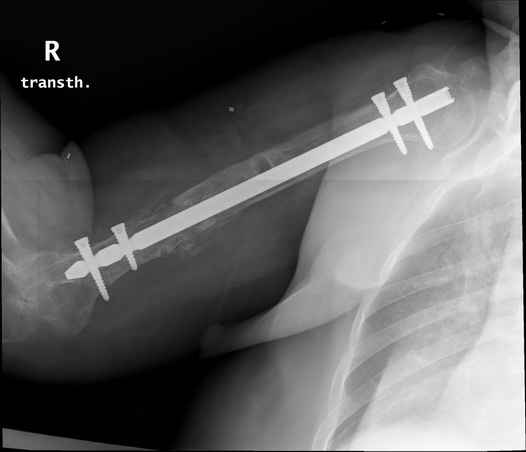

Больная 48 лет, медсестра-массажист, перелом плеча 7 лет назад, оперирована 4-кратно и безуспешно

Больная 48 лет, медсестра. Травма получена 7 лет назад, оперирована первично в Турции - остеосинтез пластиной - несращение - реостеосинтез стержнем там же через год (обычным, с выстоянеием его в полость плеча) - несращение - поступила к нам впервые в марте 2008 года - удаление стержня, реостеосинтез пластиной и костная пластика, в течение 2 лет лизис кости вокруг винтов, смещение фиксатора, в марте 2010 - удаление пластины, реостеосинтез интрамедуллярным стержнем с блокированием (рассверливание + костная пластика). В динамике - вновь лизис в области перелома, нестабильность дистальных блокирующих винтов.

Да, принципиально что-то такое тут подошло бы. Но тут дефект, и надо точно подсчитать, не длинноват ли стержень, а то, может, после плотного контакта он вылезет в локтевую ямку.

Клинически фиксация пока действительно стабильна, но на рентгенограммах резорбция кости в области дистальных блокирующих винтов и миграция одного из них.